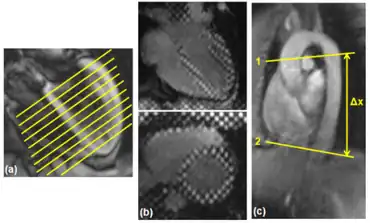

Diastolic heart failure a)measure of the filling pattern and myocardial thickness b) measure of myocardial strain c) measure of the pulse wave velocity

HFpEF is typically diagnosed with echocardiography. Techniques such as catheterization are invasive procedures and thus reserved for patients with co-morbid conditions or those who are suspected to have HFpEF but lack clear non-invasive findings. Catheterization does represent are more definitive diagnostic assessment as pressure and volume measurements are taken simultaneously and directly. In either technique, the heart is evaluated for left ventricular diastolic function. Important parameters include, rate of isovolumic relaxation, rate of ventricular filling, and stiffness.